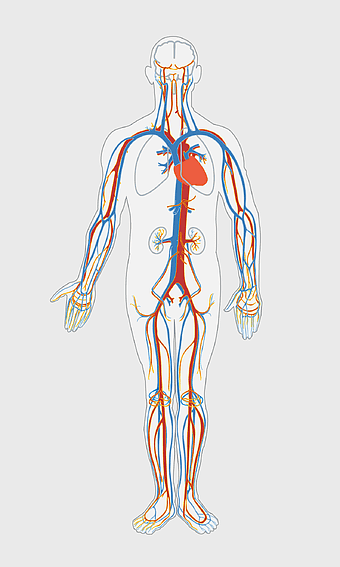

human circulatory system diagram, blood vessel network illustration, human anatomy chart, cardiovascular system overview, human body medical illustration, physiological system depiction, organ function visualization -

425x1300px

human anatomy illustration, family medicine clinic visuals, blood pressure monitoring, shoulder and hip anatomy, medical diagram of human body, circulatory system depiction, health clinic -

871x1011px

blue human anatomy illustration, human circulatory system diagram, digital human skeleton image, electric blue medical figure, human nervous system visualization, human body organ map, human health care graphic -

400x1549px